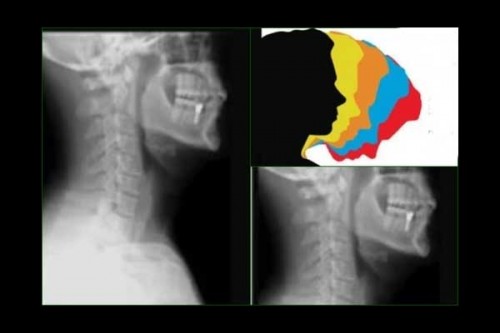

Faridabad, Oct 16 (IANS) There has been a significant rise in "text-neck syndrome", especially among the young adults, which account for about 70 per cent in the outpatient department, said city doctors on Monday on the occasion of World Spine Day.

According to doctors at Amrita Hospital Faridabad, exposure to long hours in front of screens, coupled with poor posture and inadequate ergonomics in the workplace, is causing the young adults to be susceptible to spine-related conditions like "text-neck syndrome".

The syndrome can be defined as where the neck muscles become strained and stiff, causing long-term spinal complexities, the experts said.

"Poor posture has become the most common cause of back and neck pain among our OPD patients. Remarkably, nearly 70 per cent of our OPD patients fall into this category. Poor screen etiquette is also a leading contributor to such pain. People often use their gadgets with their neck bent for prolonged periods, leading to a condition called "text-neck syndrome. Individuals between the ages of 25 and 45 are the most commonly affected by postural back pain," said Dr Tarun Suri, Head of Spine Surgery at Amrita Hospital Faridabad.

Studies show that poor posture is the primary cause of neck and back pain in young and mid-age individuals, leading to work loss, hospital visits, and treatment expenses. Over time, it damages spinal discs, causes muscle spasms, and may lead to chronic pain, disc degeneration, and even surgery in severe cases.